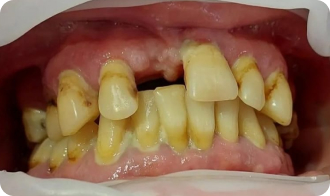

Установка All-on-4

До приёма:

• Полная адентия зубов

• Атрофия костной ткани

Результат:

• Установка имплантов Straumann

• Костная пластика

Срок: 2 дня